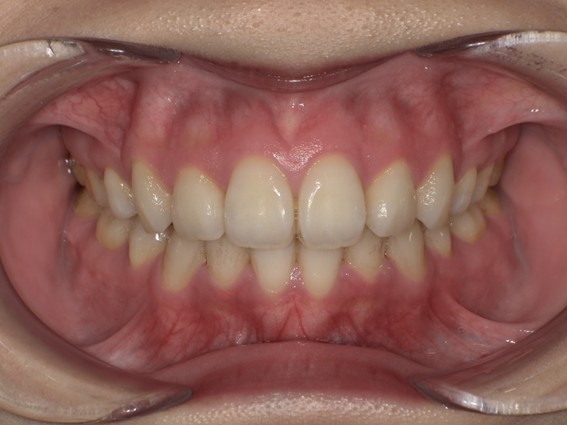

| 主訴 | 前歯が逆に噛んでいる。 |

| 治療内容 | 表側ワイヤー矯正、ジルコニア補綴を行いました。 |

| 治療費 | ワイヤー矯正660,000円(税込) ジルコニア176,000円(88,000円×2歯)(税込) |

| 治療期間 | 30ヶ月 |

| 治療回数 | 30回 |

| 想定されたリスク | 歯根吸収、歯髄壊死、歯髄充血、歯肉退縮のリスクがありました。 |

骨格性Ⅲ級・前歯部反対咬合の症例でした。反対咬合のまま治療していた前歯のサイズ不調和を、表側ワイヤー矯正とプロビジョナルクラウンで調整。正中を整え、犬歯・臼歯ともⅠ級、適切なオーバージェット(上下前歯の前後的な距離)・オーバーバイト(上下前歯の垂直的な重なり)に仕上げました。